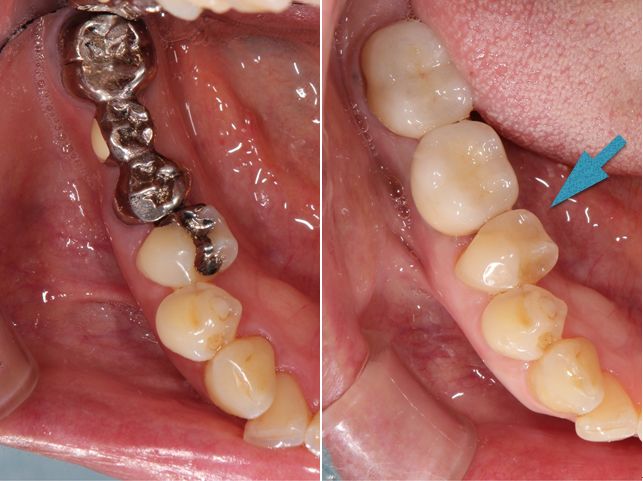

術前術後です。矢印の部分がオールセラミックインレーです。

セラミックインレー

費用11万円

リスクとして歯を削る量が多いため痛みが出る可能性と強い力によって割れる可能性がある。